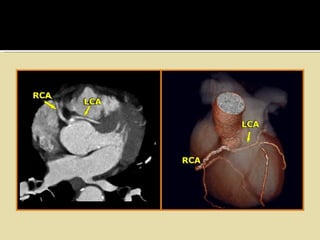

• #24 The illustration in the left upper corner is the most common and clinically significant anomaly. There is an anomalous origin of the LCA from the right sinus of Valsalva and the LCA courses between the aorta and pulmonary artery. This interarterial course can lead to compression of the LCA (yellow arrows) resulting in myocardial ischemia. The other anomalies shown do not produce hemodynamic instabilities.

• #25 Interarterial LCA On the left images of a patient with an anomalous origin of the LCA from the right sinus of Valsalva and coursing between the aorta and pulmonary artery. Sudden death is frequently observed in these patients.